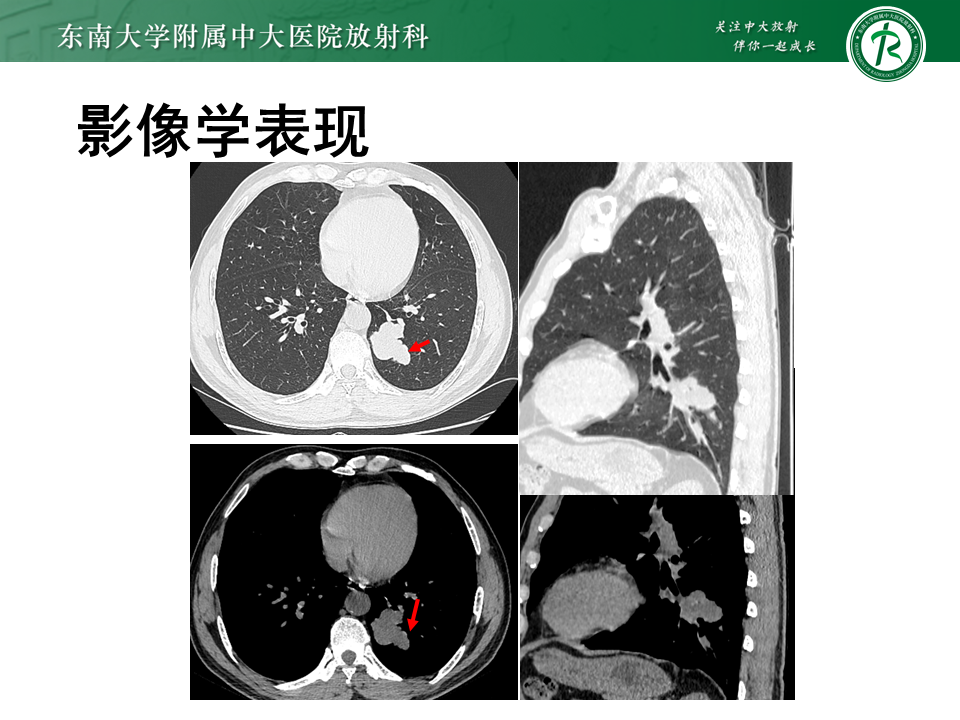

周围型肺小细胞肺癌1例|影像读片

病例1

• 男,80岁

• 主诉:发现肺结节7月余,增大2月

• 现病史:患者7月前发现肺结节,后定期复查,未特殊治疗,2月前发现结节增大伴胸闷气促,无头晕头痛,无胸痛咯血,无发热乏力,无双下肢水肿。现患者为求进一步治疗,至我院门诊就诊,门诊拟“肺结节”收治入院。病程中,患者神清、精神可,睡眠一般,食欲可,二便正常,体重无明显改变

• 个人史:既往吸烟饮酒史,现已戒烟

• 影像学检查:3536585,2025-11-10 胸部CT增强

影像学表现